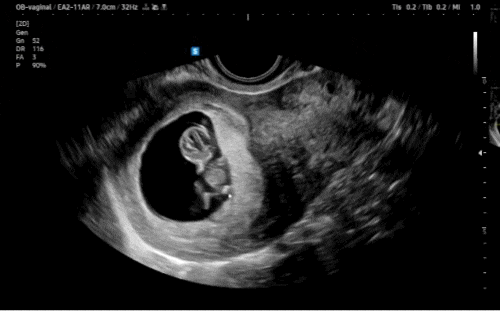

[극초기] 임신 5주 1일 ~ 7주 0일(임산부 단축근무, 평택보건소 산전검사, 임산부 뱃지, 초음파, 기형아·초음파 검사 쿠폰, 임신초기 안과, 7주차 심장소리)

아기집을 확인하고, 임신확인서를 발급받은 나는........ 공식적으로 나라에 임산부로 등록돼버려따.. 병원...